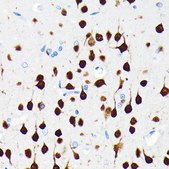

This gene encodes a member of the RNA-binding FOX protein family which is involved in the regulation of alternative splicing of pre-mRNA. The protein has an N-terminal proline-rich region, an RNA recognition motif (RRM) domain, and a C-terminal alanine-rich region. This gene produces the neuronal nuclei (NeuN) antigen that has been widely used as a marker for post-mitotic neurons. This gene has its highest expression in the central nervous system and plays a prominent role in neural tissue development and regulation of adult brain function. Mutations in this gene have been associated with numerous neurological disorders. Alternative splicing of this gene results in multiple transcript variants encoding distinct isoforms.

A synthetic peptide corresponding to a sequence within amino acids 1-100 of human NeuN (A6NFN3).

immunofluorescence: 1:50 - 1:200, immunohistochemistry: 1:50 - 1:200, western blot: 1:500 - 1:1000